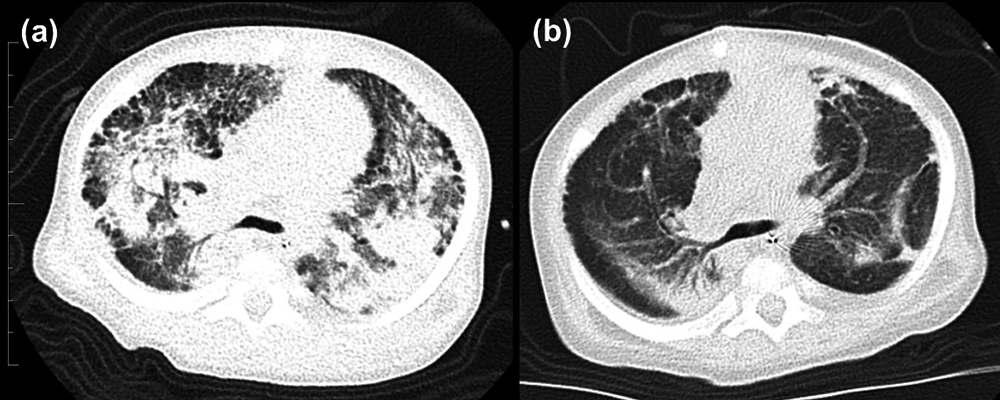

Fig. 4 Chest computed tomography illustrating fibrosis and alveolar hemorrhage

The Trisomy 21 patient has aortopulmonary window, ventricular septal defect and pulmonary stenosis. Five months after repair of aortopulmonary window, the patient developed severe respiratory failure and pulmonary hypertension. (a)The computed tomography (CT) image shows honeycomb cysts involving subpleural area, alveolar hemorrhage, parenchymal opacification consisting consolidation and ground-glass opacities. (b) Follow-up CT after steroid treatment, cessation of pulmonary vasodilators and pulmonary arterial banding shows that the findings were markedly improved.